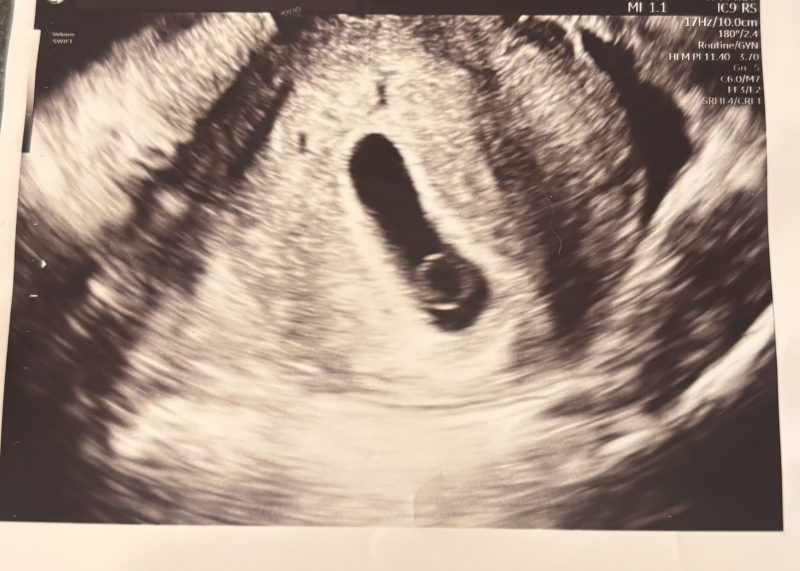

3/26日の最初の検診で胎嚢のみ確認(10.4mm)でき2週間後の4/9に2回目の検診に行ってきました。

胎嚢は(22.?mm)に大きくなっており卵黄嚢は自分の目でも確認できましたが胎芽はこれかな?というものを先生が確認していましたがまだ心拍が見えないとのことでした。

エコーで私が気になるのは卵黄嚢が大きいことです。

他の方のエコーを見ても私のものは大きめな気がします。

(卵黄嚢のサイズや胎芽のサイズなど特に先生には言われてないです)

赤ちゃんの袋の大きさ的には5~6週の前半ぐらいの大きさになるのかなとも思いました。